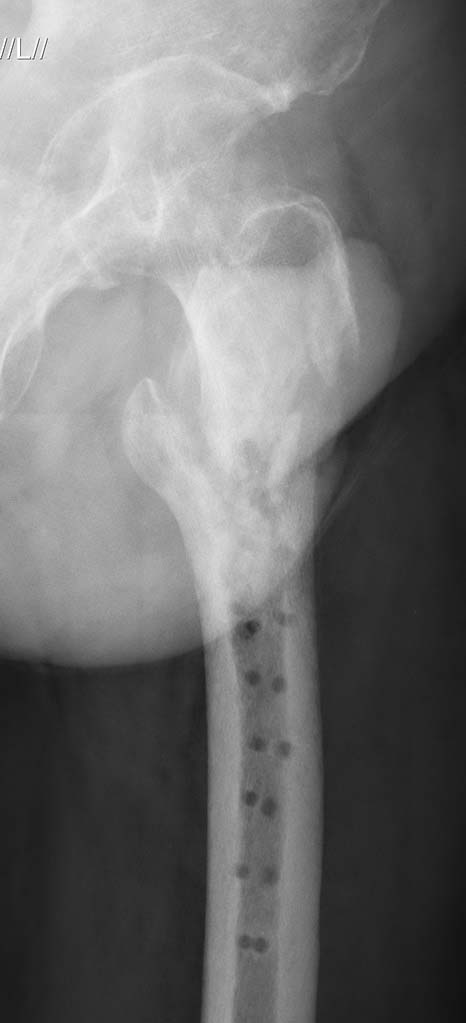

If there is no osteomyelitis, I would recommend open insertion of Gamma Nail

and Bone Grafting.

кт